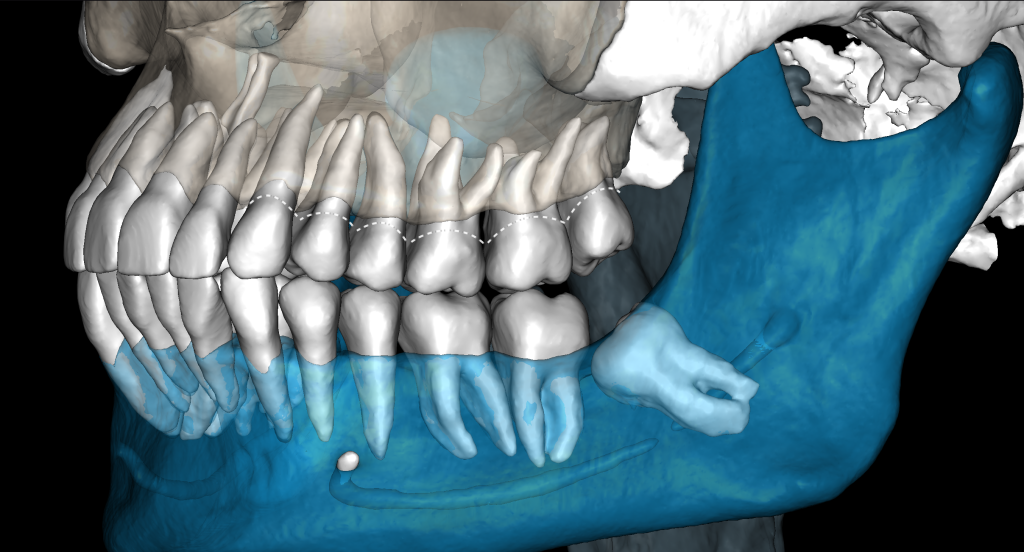

With the help of Diagnocat STL reconstruction, the doctor can visualize changes in the level of bone relative to the roots of the teeth, which are hidden behind the gum.